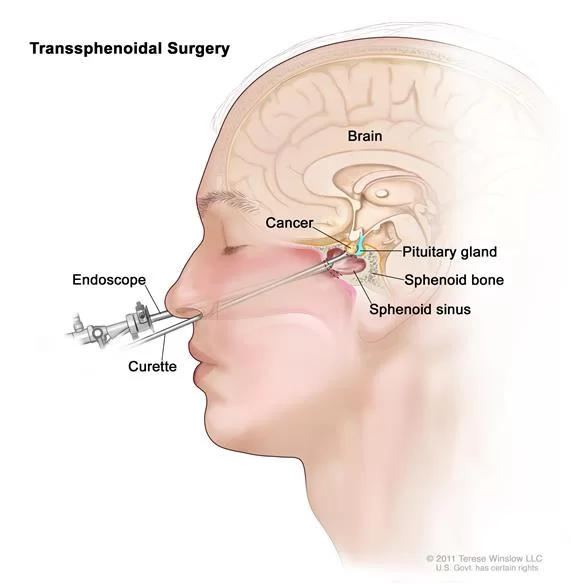

Η ενδοσκοπική επέμβαση πραγματοποιείται μέσω της μύτης για την αφαίρεση των όγκων της υπόφυσης και της βάσης του κρανίου (εικόνα 1). Σε αυτή την ελάχιστα επεμβατική χειρουργική μέθοδο, ο χειρουργός εργάζεται μέσα απο τη μύτη με μια μικρή κάμερα και φως.

- Ο χειρουργός εισάγει το ενδοσκόπιο σε ένα ρουθούνι και το προωθεί το στο πίσω μέρος της ρινικής κοιλότητας. Το ενδοσκόπιο είναι ένα λεπτό όργανο με φως και κάμερα. Το βίντεο από την κάμερα προβάλλεται σε μια οθόνη (εικόνα 2). Ο χειρουργός περνά τα εργαλεία μέσα από το ρουθούνι ενώ παρακολουθεί την οθόνη. Χρησιμοποιώντας ειδικά εργαλεία, ο χειρουργός ανοίγει το πρόσθιο τοίχωμα του σφηνοειδούς κόλπου (εικόνα 2).